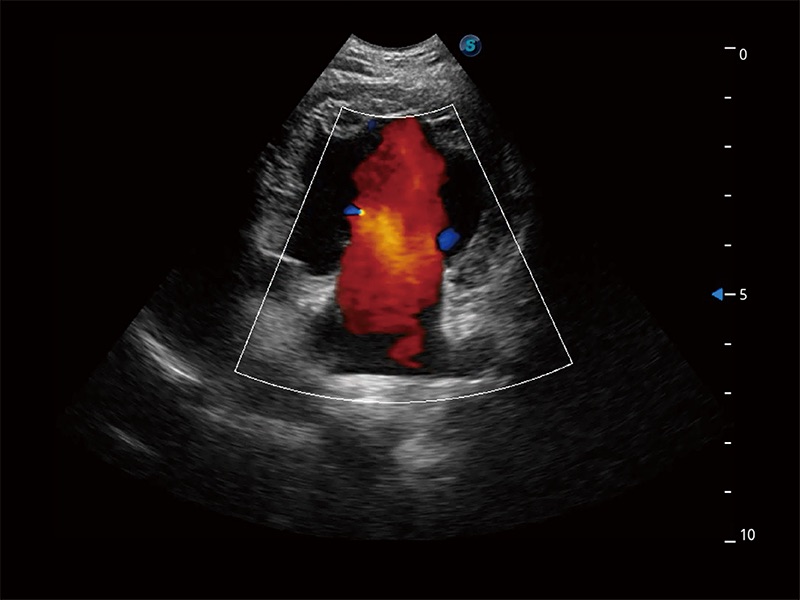

极大提升超低速微细血流的检出能力,同时更精准地滤除软组织和超声信号,为兽用医生提供以往无法通过常规血流获得的疾病诊断信息。

在传统二维血流成像的基础上,呈现血流的立体感,具有动感的生命力之美。即便是微小的血管也能轻松应对,提高了血流的视觉敏感性。

非线性融合造影成像充分利用谐波和基波信号,为难以观察的血流进行增强显像。可用于线阵、凸阵、微凸阵、相控阵探头。